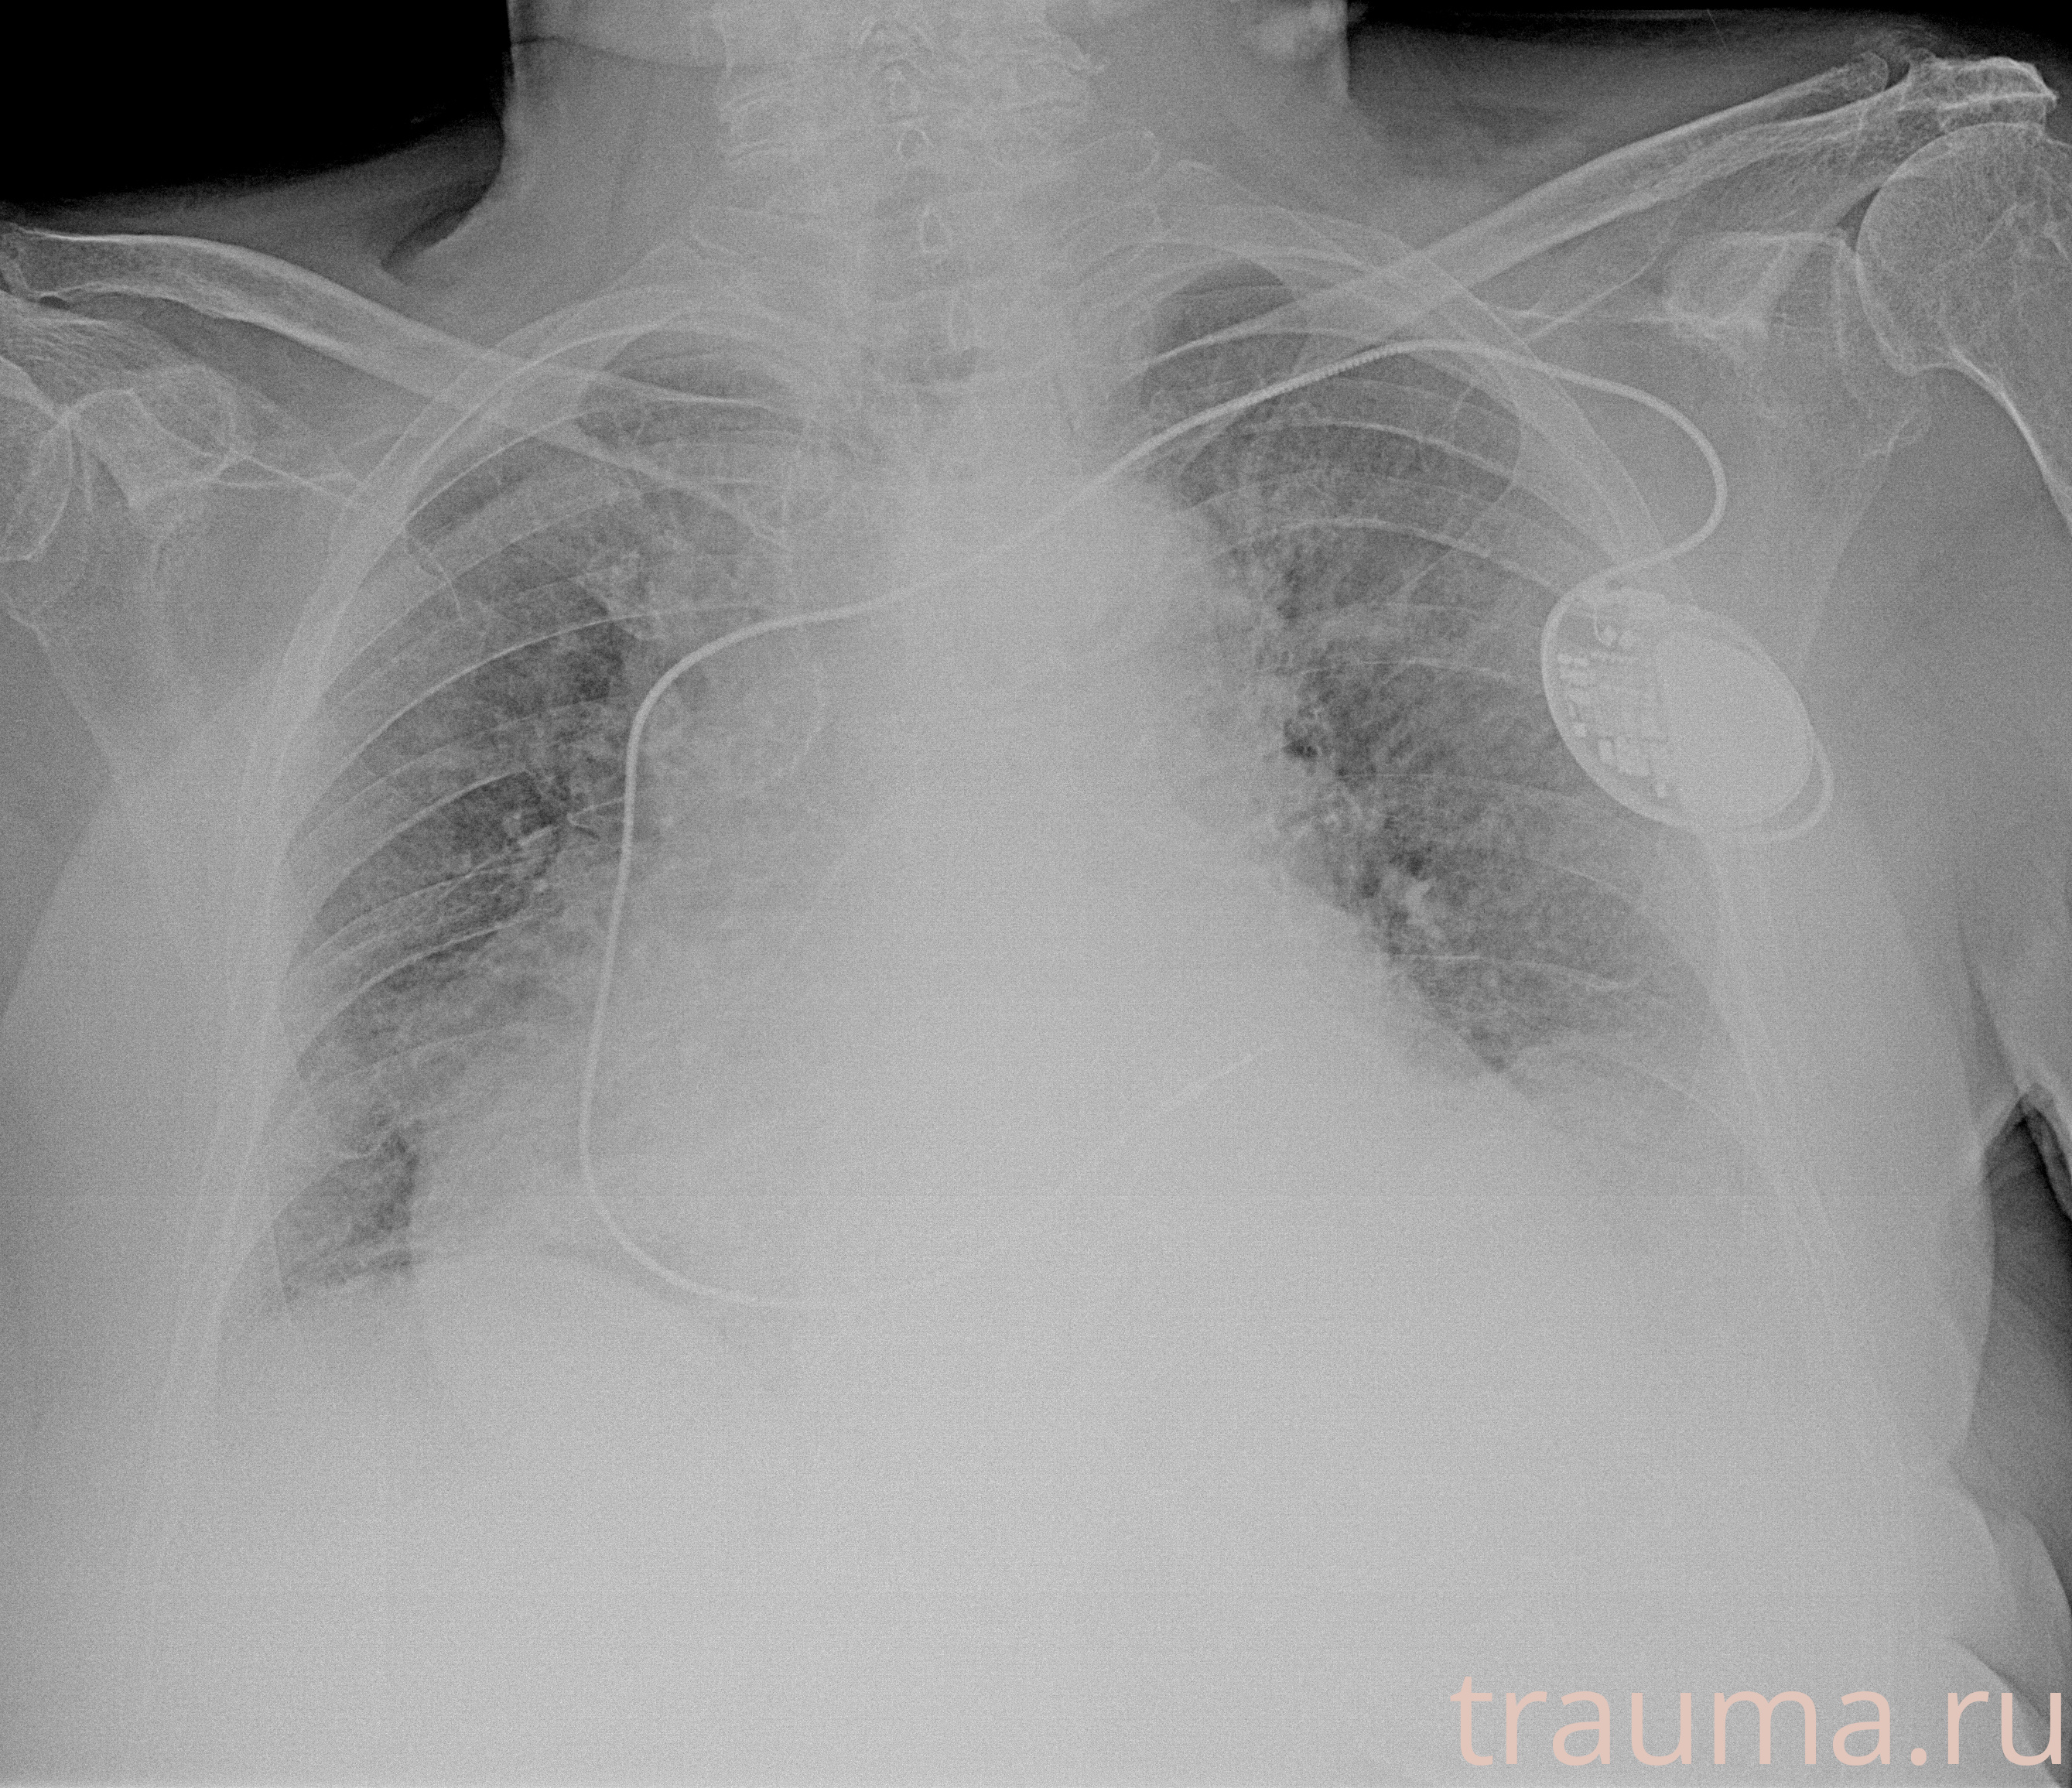

Рентгенограммы

Рентген на дому: по вашему адресу приезжает врач-рентгенолог, травматолог-ортопед с мобильным рентгеновским аппаратом, проводит диагностику травмы или заболевания, делает необходимые рентгенограммы, дает рекомендации по дальнейшему лечению. Получить качественные снимки в домашних условиях возможно благодаря уникальной методике, разработанной МосРентген Центром для института  Склифосовского

при переломе шейки бедра и пневмонии от компании МосРентген Центр - партнера Института имени Склифосовского